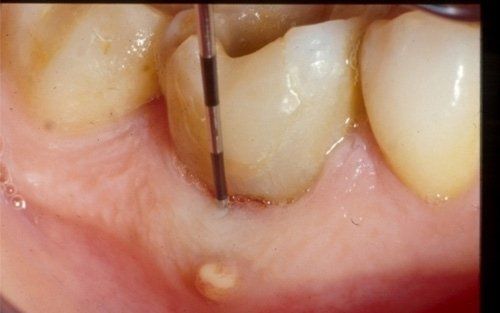

This treatment should be reserved for teeth that have irreversible pulp pathology (the nerve of the tooth) or an infection of the dental canals that has caused an abscess (acute apical periodontitis) or a granuloma (chronic apical periodontitis). While in the first two cases the tooth is very painful and the patient immediately seeks the dentist, the case of the chronic form is often silent, and therefore the patient may not notice anything for a medium to long period of time. In such conditions, it is only an X-ray image, taken during routine check-ups, that detects its presence. Root canal therapy can be completed by placing a latest-generation post inside the canal, as a means of retaining the material used for the reconstruction of the tooth. It will be up to the clinician to decide whether or not the restoration requires this additional anchoring system.